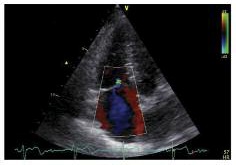

В связи с сохраняющейся одышкой, перебоями в работе сердца, сердцебиением в сентябре 2018 г. на фоне регулярного приема апиксабана пациентка направлена в НИИ кардиологии Томского НИМЦ. По данным ЭхоКГ камеры сердца не расширены. Гипертрофии нет. Глобальная сократительная функция желудочков в норме (фракция выброса по Simpson – 60%). Нарушений локальной сократимости не выявлено. Диастолическая функция левого желудочка не нарушена. Трикуспидальная регургитация 0–1-й степени, функция клапана не нарушена. Cистолическое давление в правом желудочке 26 мм рт. ст. Жидкости в полости перикарда не выявлено (рис. 5–7).

Рис. 5. ЭхоКГ, апикальная четырехкамерная позиция. Примечание. RV - правый желудочек, LV - левый желудочек, Ao - аорта, RA - правое предсердие, LA - левое предсердие.

Рис. 6. ЭхоКГ, правые отделы, трикуспидальная регургитация 0-1-й степени.

Рис. 7. ЭхоКГ, постоянно-волновое исследование трикуспидальной регургитации из апикальной четырехкамерной позиции, измерение систолического давления в правом желудочке.

По данным чресприщеводной ЭхоКГ тромбоза камер сердца не обнаружено, однако уровень D-димера – более 250 мкг/л. Исследования в отношении патологии гемостаза выявили значительный дефицит протеинов С и S. Проведена замена апиксабана на ривароксабан 15 мг 2 раза в сутки с последующим переводом на прием ривароксабана 20 мг 1 раз в сутки в связи с большей биодоступностью последнего. Также с целью усиления антитромботического эффекта к терапии добавлен клопидогрел в дозе 75 мг в сутки. При проведении СКТ органов грудной клетки с контрастированием легочной артерии 26.09.2018 выявлена положительная динамика (см. рис. 1, б, рис. 4). Состояние стабилизировалось, рецидивы одышки прекратились. От имплантации кава-фильтра пациентка отказалась.